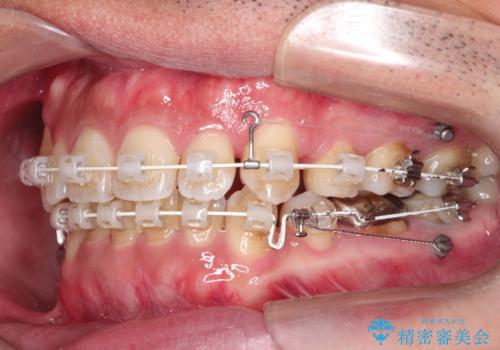

初診時の歯並びの状態としては、右上の犬歯がいわゆる八重歯の状態であり、強いガタガタが上下ともにある状態でした。

スペースの不足量が多く、抜歯を伴うワイヤー矯正にて治療を行いました。

若干の口元の突出感もあったため、抜歯によるスペースを利用し、がたつきの改善と前歯の後退をを行いました。